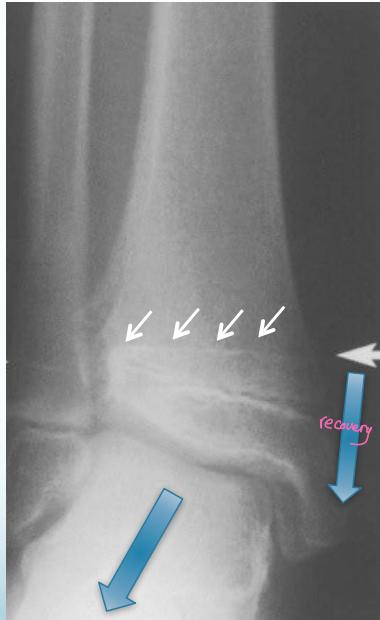

Injured and uninjured wrists after premature physeal closure

Asymmetrical Physeal Affection

- Seen on x-ray

- One side grows more than the other

- Causing an increasing deformity

- Oblique Park-Harris growth arrest/recovery line (white arrows)